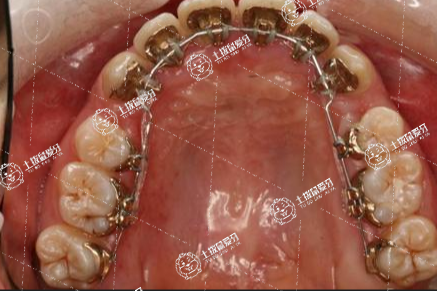

所謂的舌側(cè)隱形矯正就是將矯治器粘貼于牙齒的舌側(cè)面,牙齒矯正過程中并不會被人發(fā)現(xiàn)。但舌側(cè)隱形矯正相比唇側(cè)較復(fù)雜些,對正畸醫(yī)師操作的要求較高,技術(shù)難度較大,所以費用也會相對高一些。

舌側(cè)隱形牙齒矯正器